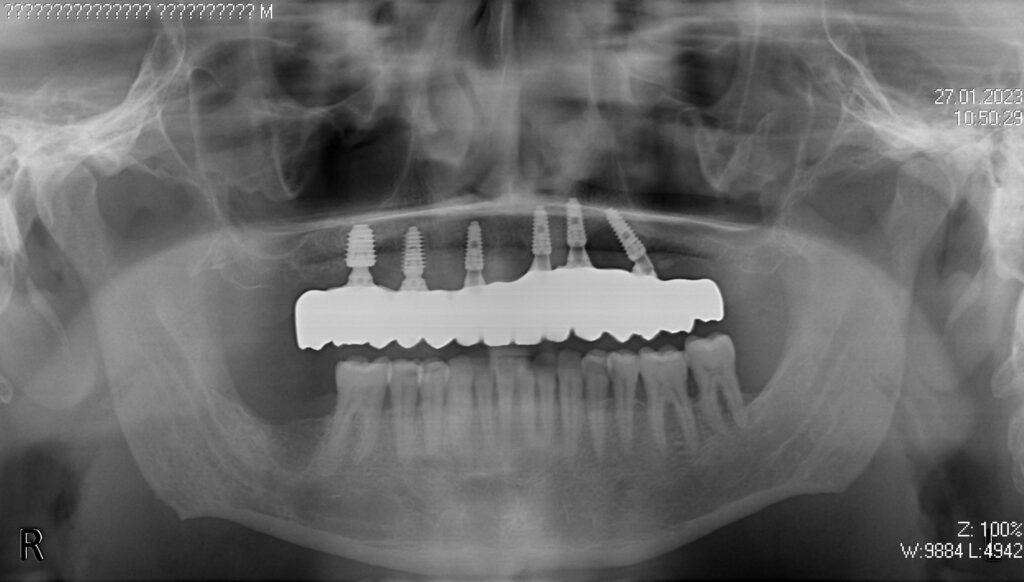

Пациент продолжает лечение спустя 3 месяца после имплантации и установки временного металлоакрилового протеза с опорой на 6-ти дентальных имплантантах Megagen Anyone.

Лечение начато с выбора материала для будущей конструкции (диоксид циркония на титановой балке) и цвета.

Спустя 25 дней был зафиксирован протез с опопрой на дентальные имплантаты из диоксида циркония с армированием из титана.